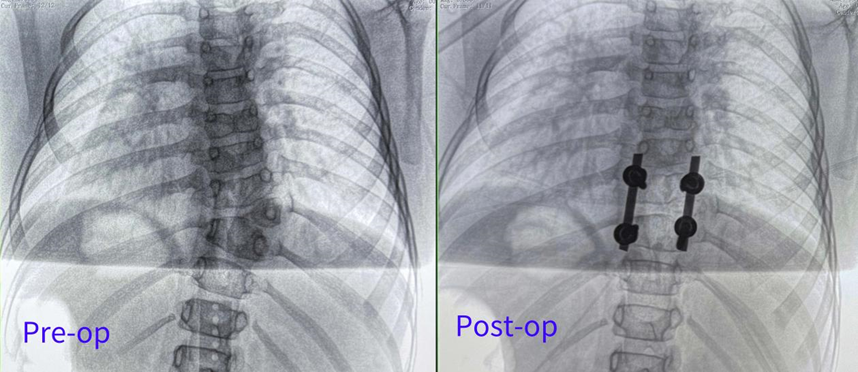

Surgical Approach: Posterior hemivertebrectomy combined with short-segment fixation and fusion

Surgical Goals: Eliminate the deforming element, correct spinal deformity, restore spinal balance, and preserve the patient's growth potential

Preoperative AP and Lateral Views

The orthopedic team at Children's Hospital of Nanjing Medical University successfully concluded this challenging procedure through the perfect synergy of surgical expertise and advanced technology. Their achievement not only restored the patient's spinal alignment but also safeguarded her ability to embrace future with confidence.